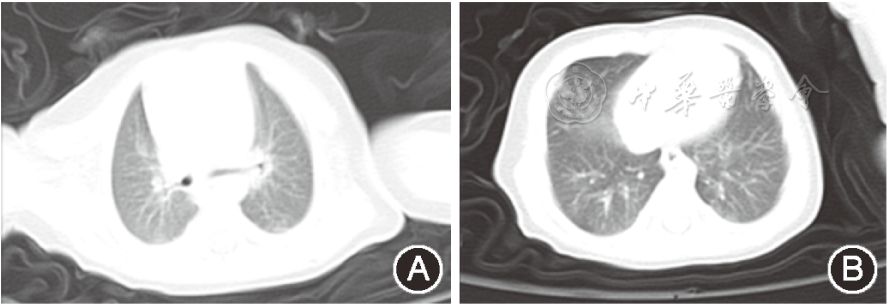

图1 新生儿新型冠状病毒感染肺炎入院当天胸部CT图片(可见两肺纹理增强,双肺叶内可见散在小条状模糊影);A:上肺;B:下肺

影像学改变于入院第6天肺部病灶吸收好转。

感染肺炎入院第6天床旁胸部X线片,可见部分左下、右上肺少许模糊影;

与入院当天肺部CT相比,病灶有吸收好转